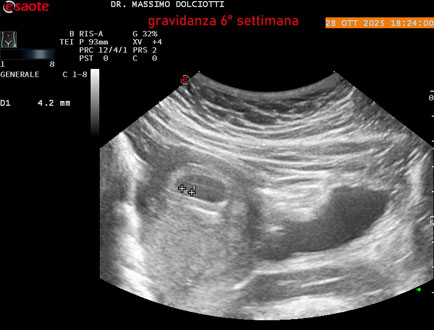

Data inserimento: 29/10/2025

Ecografia del: 28/10/2025

Strumento: Esaote MyLab Eight

Sonda: Convex Multifrequenza 1-8 MHz

Età Paziente: F 35 anni

Motivazione dell'esame: amenorrea.

Commento all'esame: le immagini ed il video documentano in utero il sacco gestazionale, il sacco vitellino e presenza di embrione delle dimensioni di 4,7 mm (CRL), con iniziale attività cardiaca, documentata nel video.

Conclusioni: gravidanza alla 6° settimana di gestazione (pregnancy to the 6th week of gestation).

Presentazione: Dr. Massimo Dolciotti - Ancona

Elaborazione digitale: Andrea Dini - Ancona